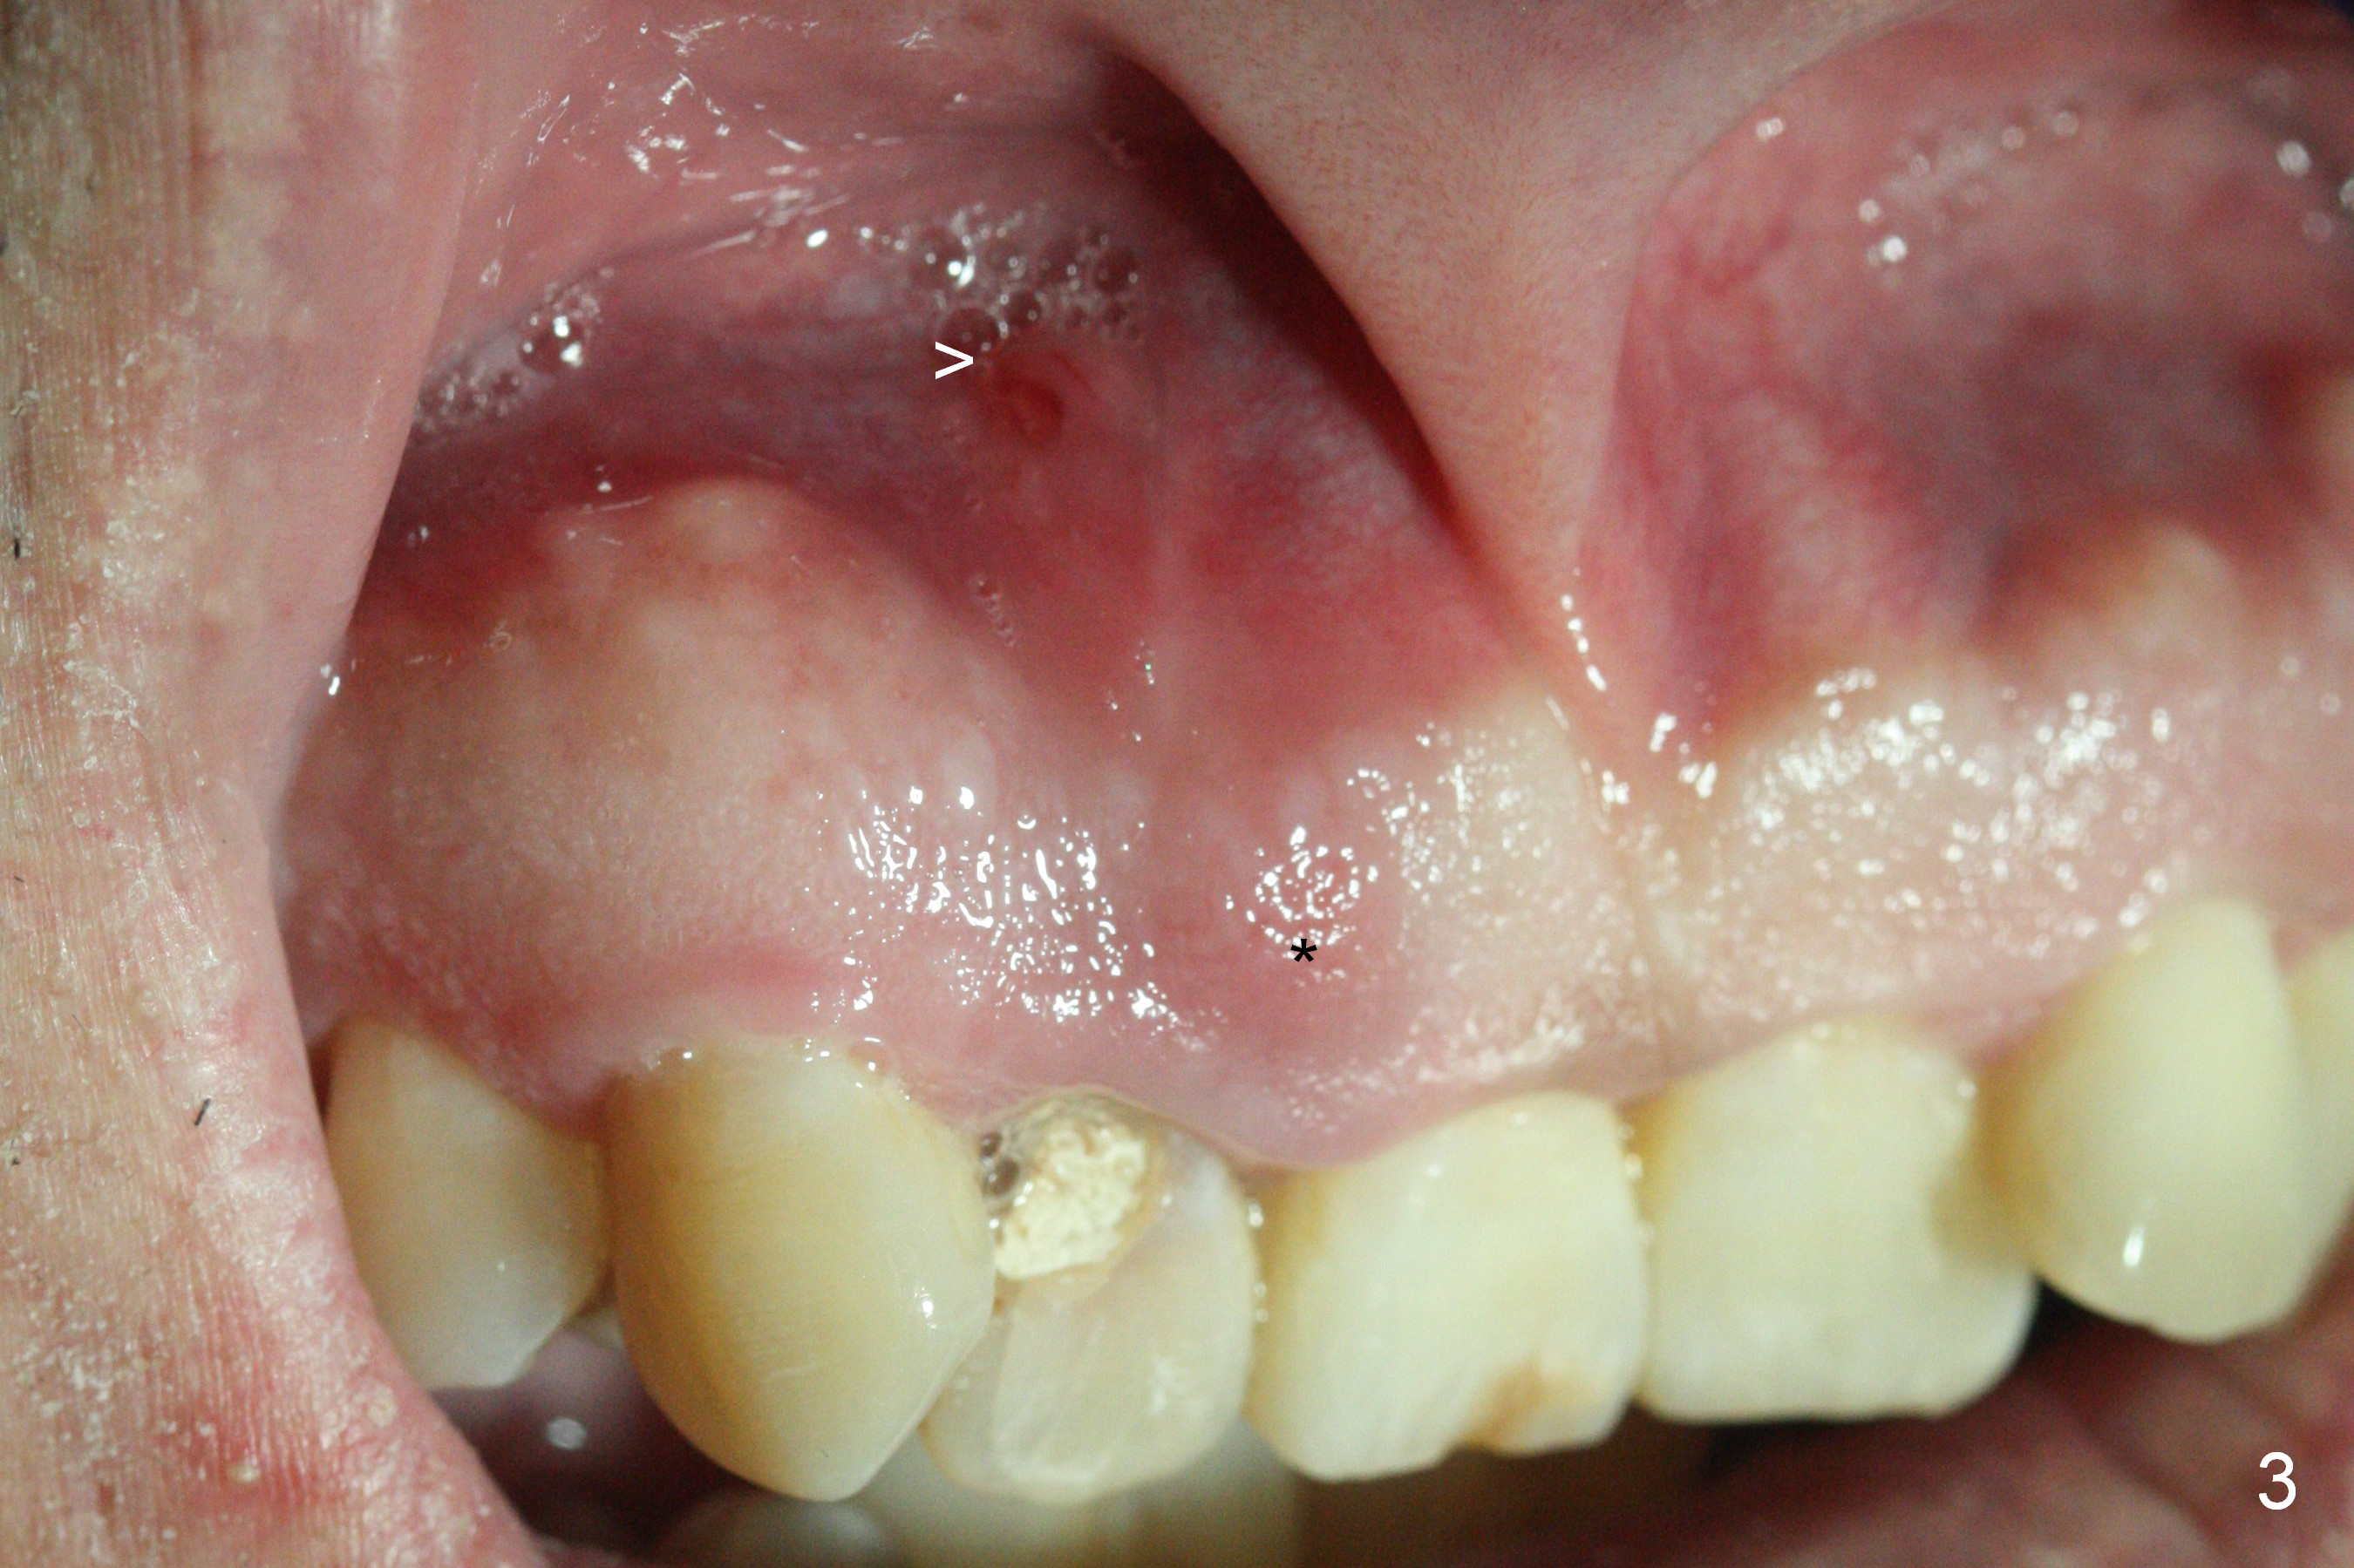

A 52-year-old man had a non-restorable lateral incisor 3 years ago (Fig.1). It fractures lately (Fig.2) with a buccal abscess (Fig.3 *) ) and fistula (>, possible severe buccal plate defect, prepare PRF). Severe deep bite (Fig.4) and malocclusion (Fig.5) will present a challenge to implant provisional restoration.

If the deep bite is a problem, place a healing abutment or the immediate provisional without the palatal apical wall. Or ask the patient in advance whether the right lateral can be placed as labial as the tooth #10 or not (Fig.3-5).